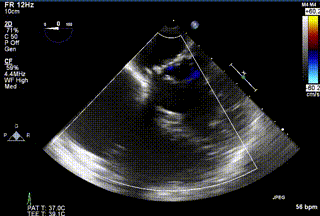

2021年12月24日,復(fù)旦大學(xué)附屬中山醫(yī)院葛均波院士團(tuán)隊(duì)成功應(yīng)用LuX-Valve Plus為一例極重度三尖瓣反流(TR)合并房顫、房缺的患者完成了經(jīng)血管三尖瓣置換術(shù),這是在前基礎(chǔ)上,本周完成的第三例經(jīng)血管三尖瓣置換手術(shù),葛均波院士、周達(dá)新教授等與心外科魏來(lái)教授、賴顥教授,心超室的潘翠珍教授、李偉教授及麻醉科的郭克芳教授共同完成了本周手術(shù),均獲得圓滿成功!患者術(shù)后超聲顯示無(wú)TR,臨床癥狀明顯改善。本周手術(shù)的成功也為L(zhǎng)uX-Valve Plus救治性臨床研究添上了濃墨重彩的一筆。

三例患者入院后,葛均波院士團(tuán)隊(duì)周達(dá)新教授、潘文志教授、張?jiān)床┦?、陳莎莎博士及心超室的潘翠珍教授、李偉教?/strong>對(duì)患者的情況進(jìn)行詳細(xì)評(píng)估和討論,最終決定為三例患者選擇LuX-Valve Plus40mm、50mm和50mm型號(hào)的瓣膜進(jìn)行手術(shù)治療。手術(shù)后即刻拔除氣管插管,術(shù)后患者三尖瓣反流癥狀得到顯著改善,復(fù)查心超結(jié)果顯示人工三尖瓣瓣膜支架固定穩(wěn)定,瓣葉關(guān)閉形態(tài)未見(jiàn)異常,未見(jiàn)明顯反流。